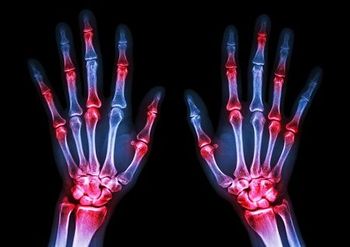

Patients with rheumatoid arthritis receiving combination treatment were more likely to reach ACR20, ACR50, and ACR70 than those receiving methotrexate monotherapy.